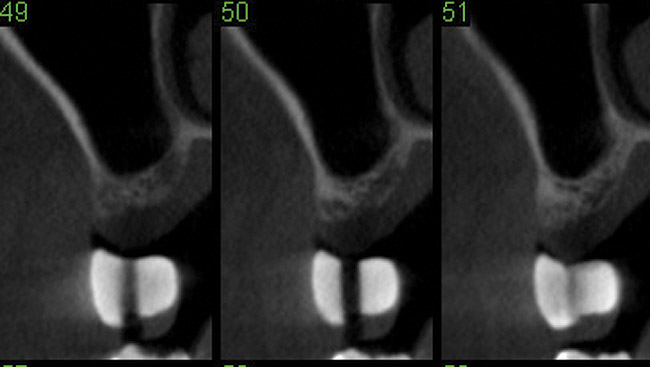

Fig 16. Sinus floor augmentation using the balloon technique. Cone-beam computed tomography of a missing upper first molar prior to sinus floor augmentation.